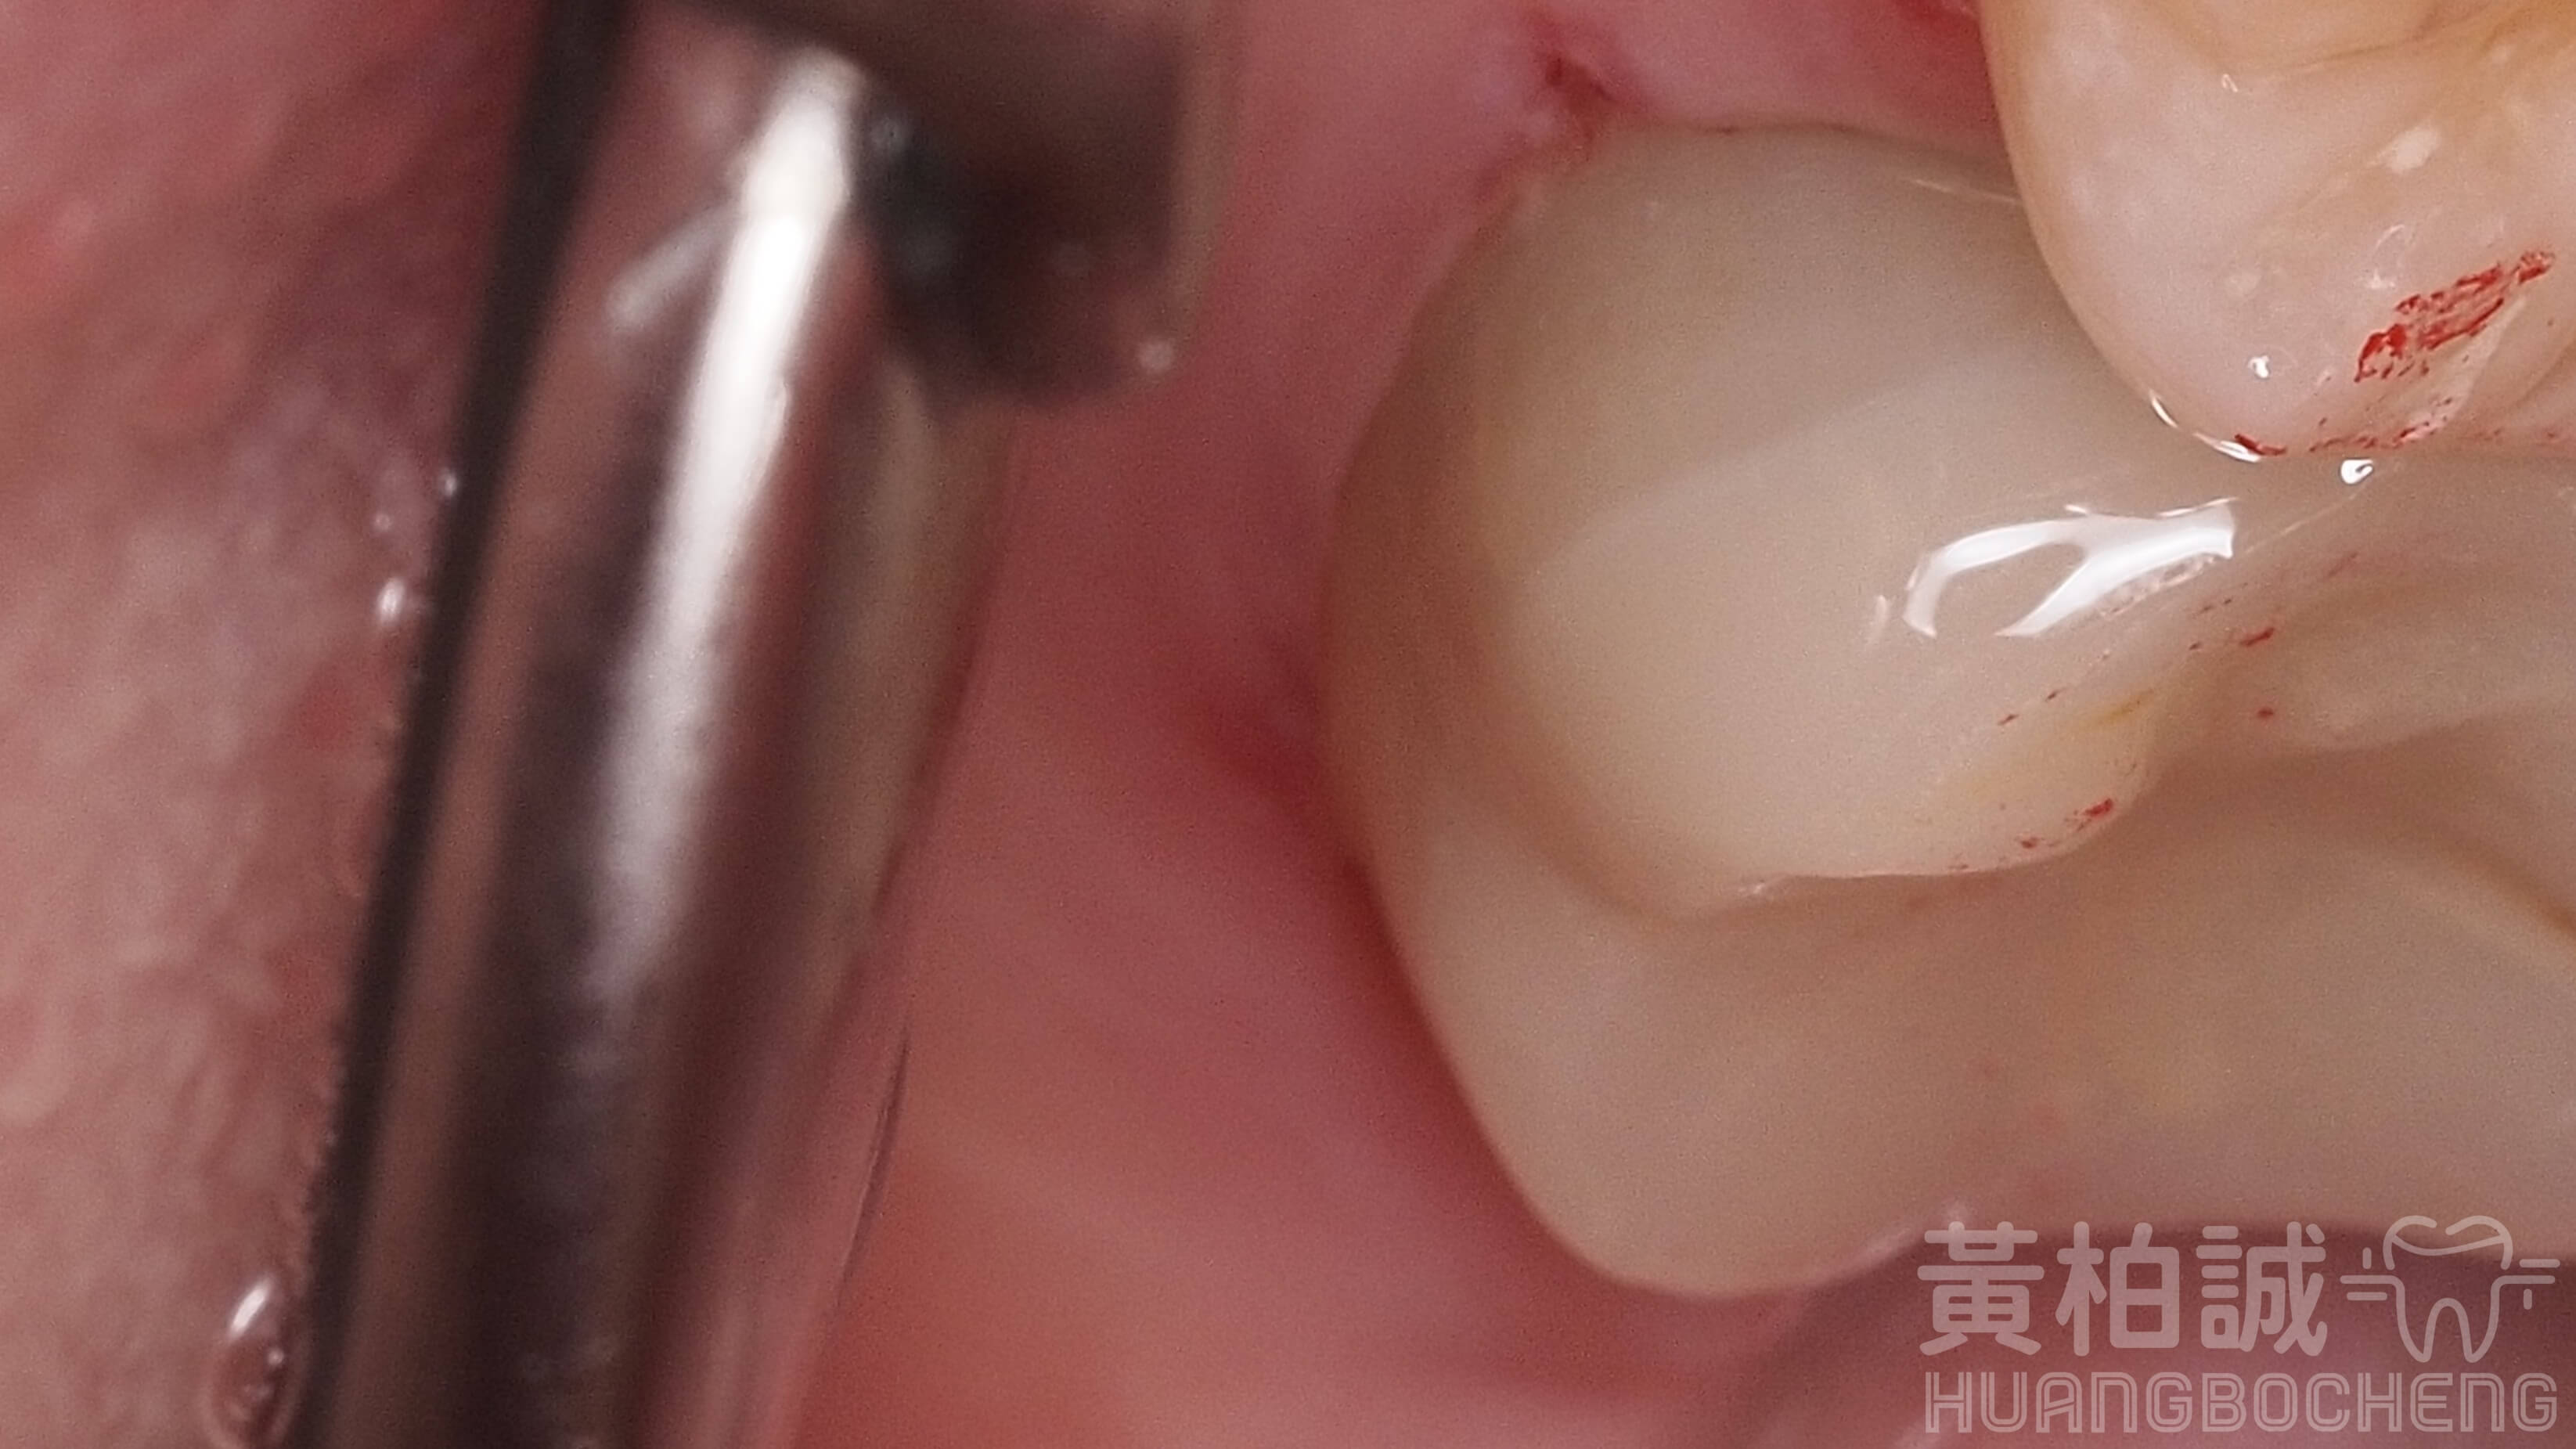

一個完美的3D齒雕應該要看起來與患者的牙齒會是嚴絲合縫的狀態,密合到幾乎看不出任何接隙存在的。

只有這樣嚴絲合縫的品質才能讓患者使用長長久久、不粗糙刮舌、並且大幅避免未來齒質再次崩壞的機率。